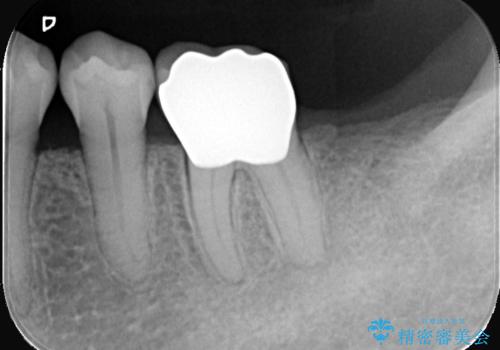

治療では、破損した古いレジンを除去し、セラミッククラウンを装着するための形を整えました。

広範囲にわたる欠損をセラミッククラウンで覆うことにより、咬合時の負担が歯の一部に集中するのを防ぎ、歯根の破折リスクを大幅に軽減させています。精密に作製されたセラミックは適合性に優れており、歯との段差がほとんどないため、細菌が入り込みにくい清潔な状態を作ることができます。

修復後は、天然歯のような美しい見た目はもちろん、硬いものでもしっかりと噛める強度が備わりました。適合精度と耐久性が向上したことで、将来的に再治療が必要になるリスクを最小限に抑えた、安心できる口腔環境を取り戻していただけました。